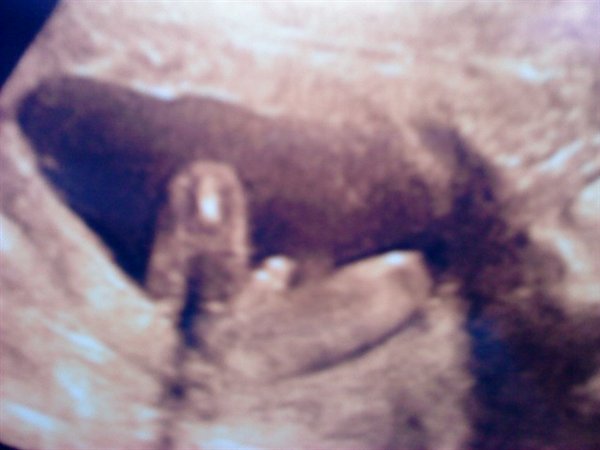

Her er et billede, og der er vist ingen tvivl.. Vi venter os en lille fræk dreng :-)

Tillykke med ham ! Der er vist ingen tvivl om at det er en dreng ahahah!